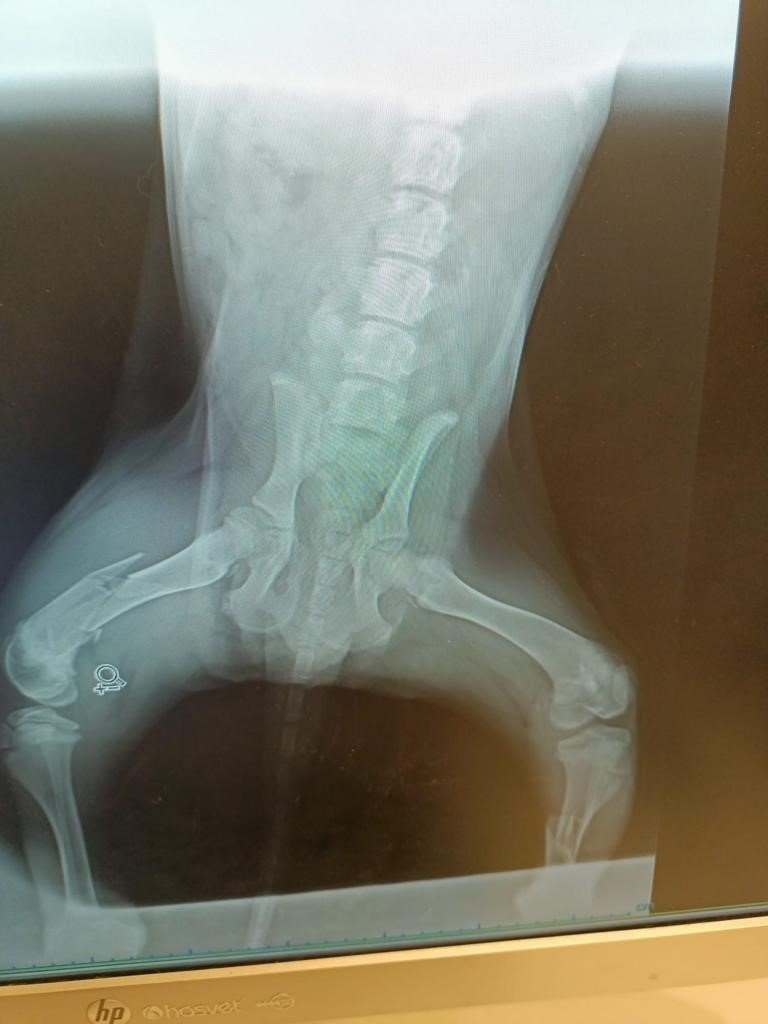

Olay geçtiğimiz cumartesi günü 75. Yıl Mahallesi'nde meydana geldi. Güvenlik kamerasına yansıyan görüntüde, annesiyle birlikte karşıdan karşıya geçmeye çalışan yavru köpeğe çarpan araç şoförünün, durmadan yoluna devam ettiği görüldü. Kazada iki bacağı birden kırılan yavru köpek, o esnada olayı gören bir hayvan sever tarafından iş yerinde gözlem altına alındı. Daha sonra köpeğin yaralarının ciddi olduğu anlaşılınca Eskişehir Hayvanları Koruma, Yaşam Haklarını Savunma ve Yardımlaşma Derneği Başkanı Nesrin Çiçek'e haber verildi. Hayvan severlerin çabaları sayesinde özel bir kliniğe kaldırılan yavru köpeğin her iki bacağına da protez takıldı. Yavru köpeğe çarpıp kaçan şoför hakkında şikayetçi olduklarını dile getiren Çiçek, bir çok vatandaşın kaza yaptıktan sonra hayvanları terk ettiğini belirtti.

Kazaya karışan kişilerin hayvanlara müdahale etmesi durumunda sigortalarının klinik masraflarını karşıladığından bahseden Nesrin Çiçek, insanların bunu bilmediği için hayvanlara çarptıktan sonra kaçtıklarını söyledi. Üç aylık yavru köpeğin tedavisine başlandığını anlatan Çiçek, "Olay bize Cumartesi günü saat 13.00 sularında intikal etti. Besleme noktamızda bir kışın doğan, yani 3 aylık civarında olan canlardan birine araç çarptığını bölgede besleme yapan arkadaşlarımızdan öğrendik. "Durumunu tam olarak bilemiyorum" dediği için Odunpazarı Bakım Evi'ni aramalarını söyledim. Daha sonra hayvanın bacaklarının üstüne kalkamadığını anlayınca bakımevi aracılığı ile özel kliniğe nâkilini sağladık. Eskişehir'de iki tane bakımevi var ve maalesef ikisi de kaza geçiren hayvanlara müdahale edecek teçhizata sahip değiller. Bunun üzerine özel kliniğe aldırınca 3 aylık hayvanın iki bacağında da kırık olduğunu öğrendik. Dün her iki bacağına da protez takıldı ve sadece bunun maliyeti 12 bin lira. Eğer bize denk gelmemiş olsa bu hayvan ölüme mahkum olacak. Oradaki arkadaşlarımızın da yapabileceği çok fazla bir şey yok. Şunu da belirtmek istiyorum 5199 Sayılı Kanun sadece mevzuatta olan bir kanun gibi görülüyor. Vatandaşlara yeterli bilgilendirme yapılmadığından dolayı hayvanlara çarpan kişiler kaçıyor. Köpeği çarpıp yoluna devam kişi hakkında şikâyetlerimizi yaptık Haydi polisi plaka kişi tespitinde bulunacak, oysa çarpan kişi müdahale etmiş olsa araç sigortası klinik maliyetini karşılıyor bunu çoğu kişi bilmediği için bırakıp terk ediyor" ifadelerini kullandı.